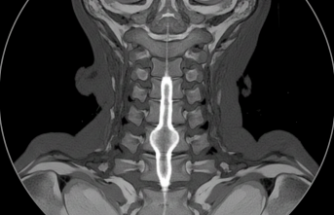

Beyinciğin aşağı doğru, omurilik kanalına doğru hafifçe kayması durumu bu. İnsan bazen merak ediyor; neden ben? Aslında çoğu zaman doğuştan gelen bir yapı meselesi. Eylül ayının serin günlerinde yapılan kontrollerde genellikle tesadüfen çıkıyor ortaya. Belki de yıllardır sizinleydi ama sessizce bekliyordu.

Klinik tablodaki belirsizlik hastaları biraz yoruyor. Yapılan tetkiklerde beyincik dokusunun kanala doğru sarktığı görülmekte. Uzman hekimler hastanın yaşam kalitesini önceliyor. Ameliyat kararı her vaka için ayrı değerlendiriliyor.